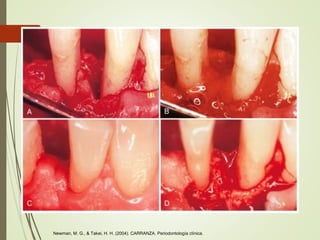

Regeneración tisular guiada

Consiste en la colocación de una

barrera para cubrir el hueso y el

ligamento, separandolos de

manera temporal del epitelio

gingival

Al separar el epitelio y el tejido conectivo de la superficie radicular

durante la cicatrización se evita la migración epitelial y favorece la

repoblación de células

No reabsorvible: politetrafluoretileno

Reabsorvible: colágenas

Newman, M. G., & Takei, H. H. (2004). CARRANZA. Periodontología clínica.

Clinical Periodontology and Implant Dentistry, Sixth Edition. Edited by Niklaus P. Lang and Jan Lindhe. © 2015 John Wiley & Sons,

Ltd. Published 2015 by John Wiley & Sons, Ltd.

E. 5 semanas para

remover membrana

F. 1 año despues

Karring, T., & Cortellini, P. (1999). Regenerative therapy: furcation defects. Periodontology 2000, 19(1), 115-137.